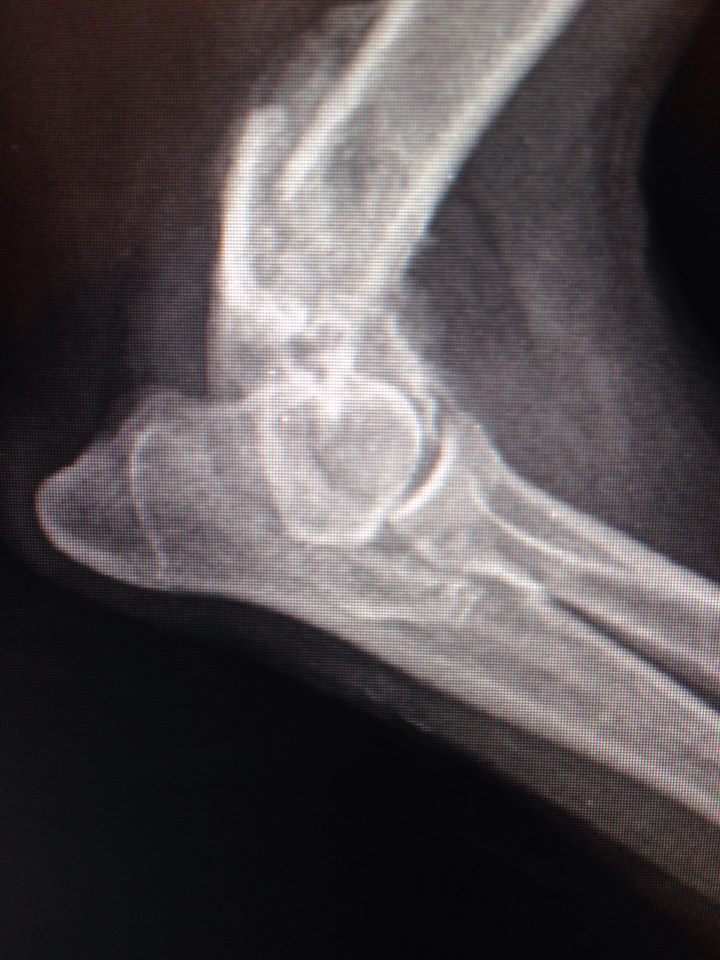

В клинику поступила с жалобами на отсутствие опоры левой грудной конечности. При осмотре обнаружилось, что у собаки нарушены анатомические контуры левого локтевого сустава и при манипуляциях с этим суставом животное испытывает боль.

Рентгенографические снимки в прямой и боковой проекциях показали, что Элли перенесла полтора-два месяца назад перелом латерального мыщелка левой плечевой кости.

Этот перелом не был должным образом пролечен. Собаке нужно было выполнить хирургическое лечение, так как такие переломы лечатся только оперативно. Все внутрисоставные переломы должны быть хирургически собраны максимально точно. Это обеспечивает полноценность работы сустава. Если нет адекватного анатомического сопоставления, будет развиваться остеоартрит, сустав придет в негодность. В данном случае собаке просто наложили гипс. За прошедшее время поверхности срослись в том виде, в каком были при переломе. Сустав полностью был разрушен.